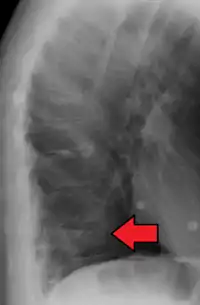

Example of vertebral compression fracture.

A compression fracture is a collapse of a vertebra. It may be due to trauma or due to a weakening of the vertebra (compare with burst fracture). This weakening is seen in patients with osteoporosis or osteogenesis imperfecta, lytic lesions from metastatic or primary tumors,[1] or infection.[2] In healthy patients, it is most often seen in individuals suffering extreme vertical shocks, such as ejecting from an ejection seat. Seen in lateral views in plain x-ray films, compression fractures of the spine characteristically appear as wedge deformities, with greater loss of height anteriorly than posteriorly and intact pedicles in the anteroposterior view.[3]

A potential complication of a vertebral compression fracture is avascular necrosis of the vertebral body, which is called Kümmel's disease, and may appear with the intravertebral vacuum cleft sign (at white arrow in image).[4]